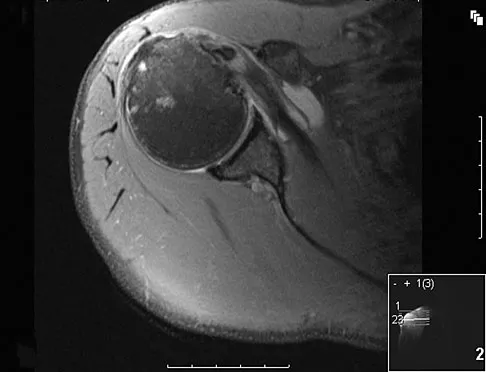

Question 51

A patient reports persistent anterior shoulder pain following a forceful external rotation injury to the shoulder. An MRI scan is shown in Figure 4. The patient remains symptomatic despite 3 months of nonsurgical management. Treatment should now consist of